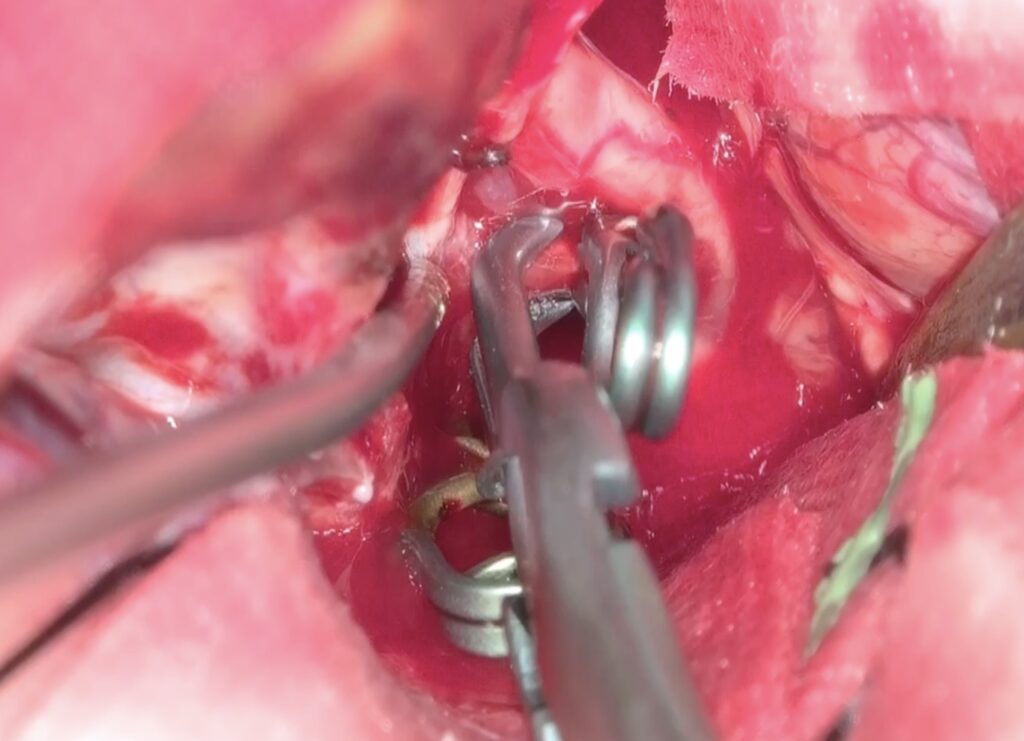

最近のこの場所の動脈瘤クリッピング術が増えています。4mm以上の上向き動脈瘤で術前BTOで虚血耐性のあるものを適応としています。ICG、MEP、VEG、術中血管撮影など術中画像、電気生理学モニタリングをしっかり準備して行っています。本例も視神経下面と癒着しており、剥がすときに破れましたが、問題なくクリップできています。術後の視機能も良好でした。

術後嗄声と2/23より髄液鼻漏れがあり、CTで左篩骨洞に髄液貯留があり5日間の腰椎ドレナージを行い、治癒しました。